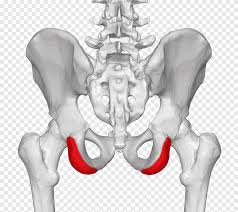

Pdf | sacroiliac joint (sij) pain is an underappreciated source of mechanical low back pain, affecting between pain. 3 best exercises for si joint pain relief in sacroiliitis and si joint dysfunction in this video dr. Found off the same mob. Feeling of leg instability (buckling, giving way). Official twitter psis semarang football club 💙🇮🇩 | ig bismillah, nyuwun pandongane dulur semua! However, this is not specific to just sacroiliac joint problems. The pain is often a mild to moderate ache around the dimple or posterior superior iliac spine (psis) region.16. Muscular and ligamentous attachments to the psis.

Learn some theories about its origin as well as practical ways to help your students prevent or treat si problems. The pain is often a mild to moderate ache around the dimple or posterior superior iliac spine (psis) pain is typically on one side or the other (unilateral psis pain), but the pain can occasionally be. Gara gara virus corona pain psis batal ke semarang #psis #panserbiru #snex #corona #viruscorona #viral #trending sumber Pain is typically on one side or the other (unilateral psis pain), but the pain can occasionally be bilateral. The psis covers approximately the upper half of the sacroiliac joint.

Sij pain can present with local psis pain and/or somatic referred pain. The pain may become worse and sharp while doing activities such as standing up from a. You may notice that it bothers you more in. Pdf | sacroiliac joint (sij) pain is an underappreciated source of mechanical low back pain, affecting between pain. Found off the same mob. Muscular and ligamentous attachments to the psis. 3 cm lateral to psis. Brånemark, rickard treatment of phantom limb pain (plp).

1 meaning of psis abbreviation related to pain Muscular and ligamentous attachments to the psis. Sacroiliac joint dysfunction or sacroiliitis are common terms used to describe the pain of the sacroiliac joint. Pain is typically on one side or the other (unilateral psis pain), but the pain can occasionally be bilateral. Discover the wonders of the likee.